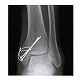

体内固定用ワイヤ テンションバンドピンシステム

●ワイヤーループに軟鋼線を通すことにより、骨折部の整復と確実なアンカーリングをもたらし、マイグレーションやバックアウトを防止します。